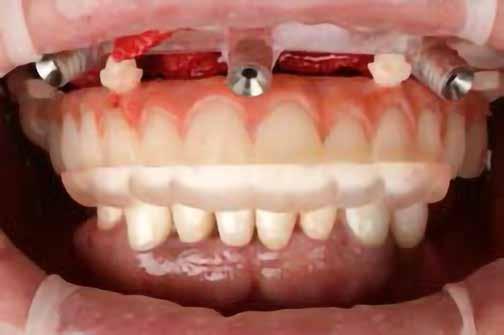

A korai harmicas éveiben járó hölgy rendelőnkbe érkezésének oka a jobb felső nagymetsző fog bizonytalan érzkenysége, elmondása alapján gyermekkorában trauma érte a felső frontrégiót. A frakturált klinikai koronákat kompozittöméssel helyreállították, egyéb kezelést akkor nem tartottak szükségesnek. Az utóbbi hónapokban tapasztalt érzékenység miatt kereste fel rendelőnket. A klinikai vizsgálat (1. és 2. kép) és a CBCT felvétel (3. kép) alapján diagnosztizált külső gyökérreszorpció megoldására a fog eltávolítását, implantátum

behelyezését, majd csavarozott rögzítésű, cirkónium-dioxid vázas, kerámialeplezésű korona készítését terveztük [1., 5., 6., 8.].

bukkális 1. kép: Kiindulási állapot, 2020. január. 3. kép: Kiindulási CBCT felvétel. 2. kép: Kiindulási állapot a palatinális oldal felől.

A behelyeztt implantátum primer stabilitását megfelelőnek ítéltük (kb. 40 Ncm) az azonnali terheléshez (9. kép).

Az extrakciót megelőző szituációs lenyomat alapján gyári, titán, ideiglenes abutment felhasználásával, a szék mellett készített, csavaros rögzítésű, azonnali akrilát ideiglenes koronával láttuk el, melyet 20 Ncm nyomatékkal rögzítettünk (10. kép). Az azonnali terhelés szabályainak megfelelően, az ideiglenes korona nem volt kontaktusban a szomszédos és az antagonista fogakkal.

6. kép: Implantátum-ágy preparáció. 7. a–b. képek: Implantátum behelyezés. 8. kép: A behelyezett implantátum. 10. a–b képek: Azonnali ideiglenes korona készítése. 9. kép: Megfelelő primer stabilitás.

10. c–d képek: A kész ideiglenes korona. 11. kép: A 6 hónapos kontroll felvétele.

A 2020 januárjában elkezdett kezeléssorozat befejezését az év márciusában, hazánkba is begyűrűző Covid-19 pandémia késleltette, így kb. 6 hónap gyógyulás után láttunk hozzá az emergencia profil és a gingivális zenit ideiglenes koronával történő formázásához (11. és 12. kép). A 3 hetente végzett apró alakításokkal sikerült megfelelő ínyprofilt kialakítani, a „rózsaszín esztétika” a páciens számára is megfelelő volt. A bal felső nagymetsző fog meziális kompozit tömés cseréjét követően, individualizált nyitott kanalas lenyomati fejet készítettünk: az akrilát ideiglenes korona profilját átlátszó szilikonnal lemásoltuk, majd a körszimmetrikus gyári lenyomati fej és az ideiglenes korona kontúrja közötti hézagot folyékony kompozittal töltöttük ki (13. kép). Az így készített egyéni lenyomati fejjel vettünk lenyomatot a végleges, kerámialeplezésű cirkónium-dioxid vázas, átmenő csavaros rögzítésű koronához. (A fogtechnikai munkát Nébl Péter fogtechnikusmester készítette.), (14., 15., 16 és 17. képek).

A kész korona átadásakor a páciens elégedett volt az esztétikával, az azóta eltelt évben rendszeres kontrollokon jelent meg, melyek során meggyőződtünk a kemény- és lágyszövetek stabilitásáról (18. és 19. képek).

17. a–b képek: A kész munka átadáskor. 18. a–c képek: 1 éves kontroll. 19. kép: Intraorális kontroll röntgen felvétele 1 évvel az átadás után.